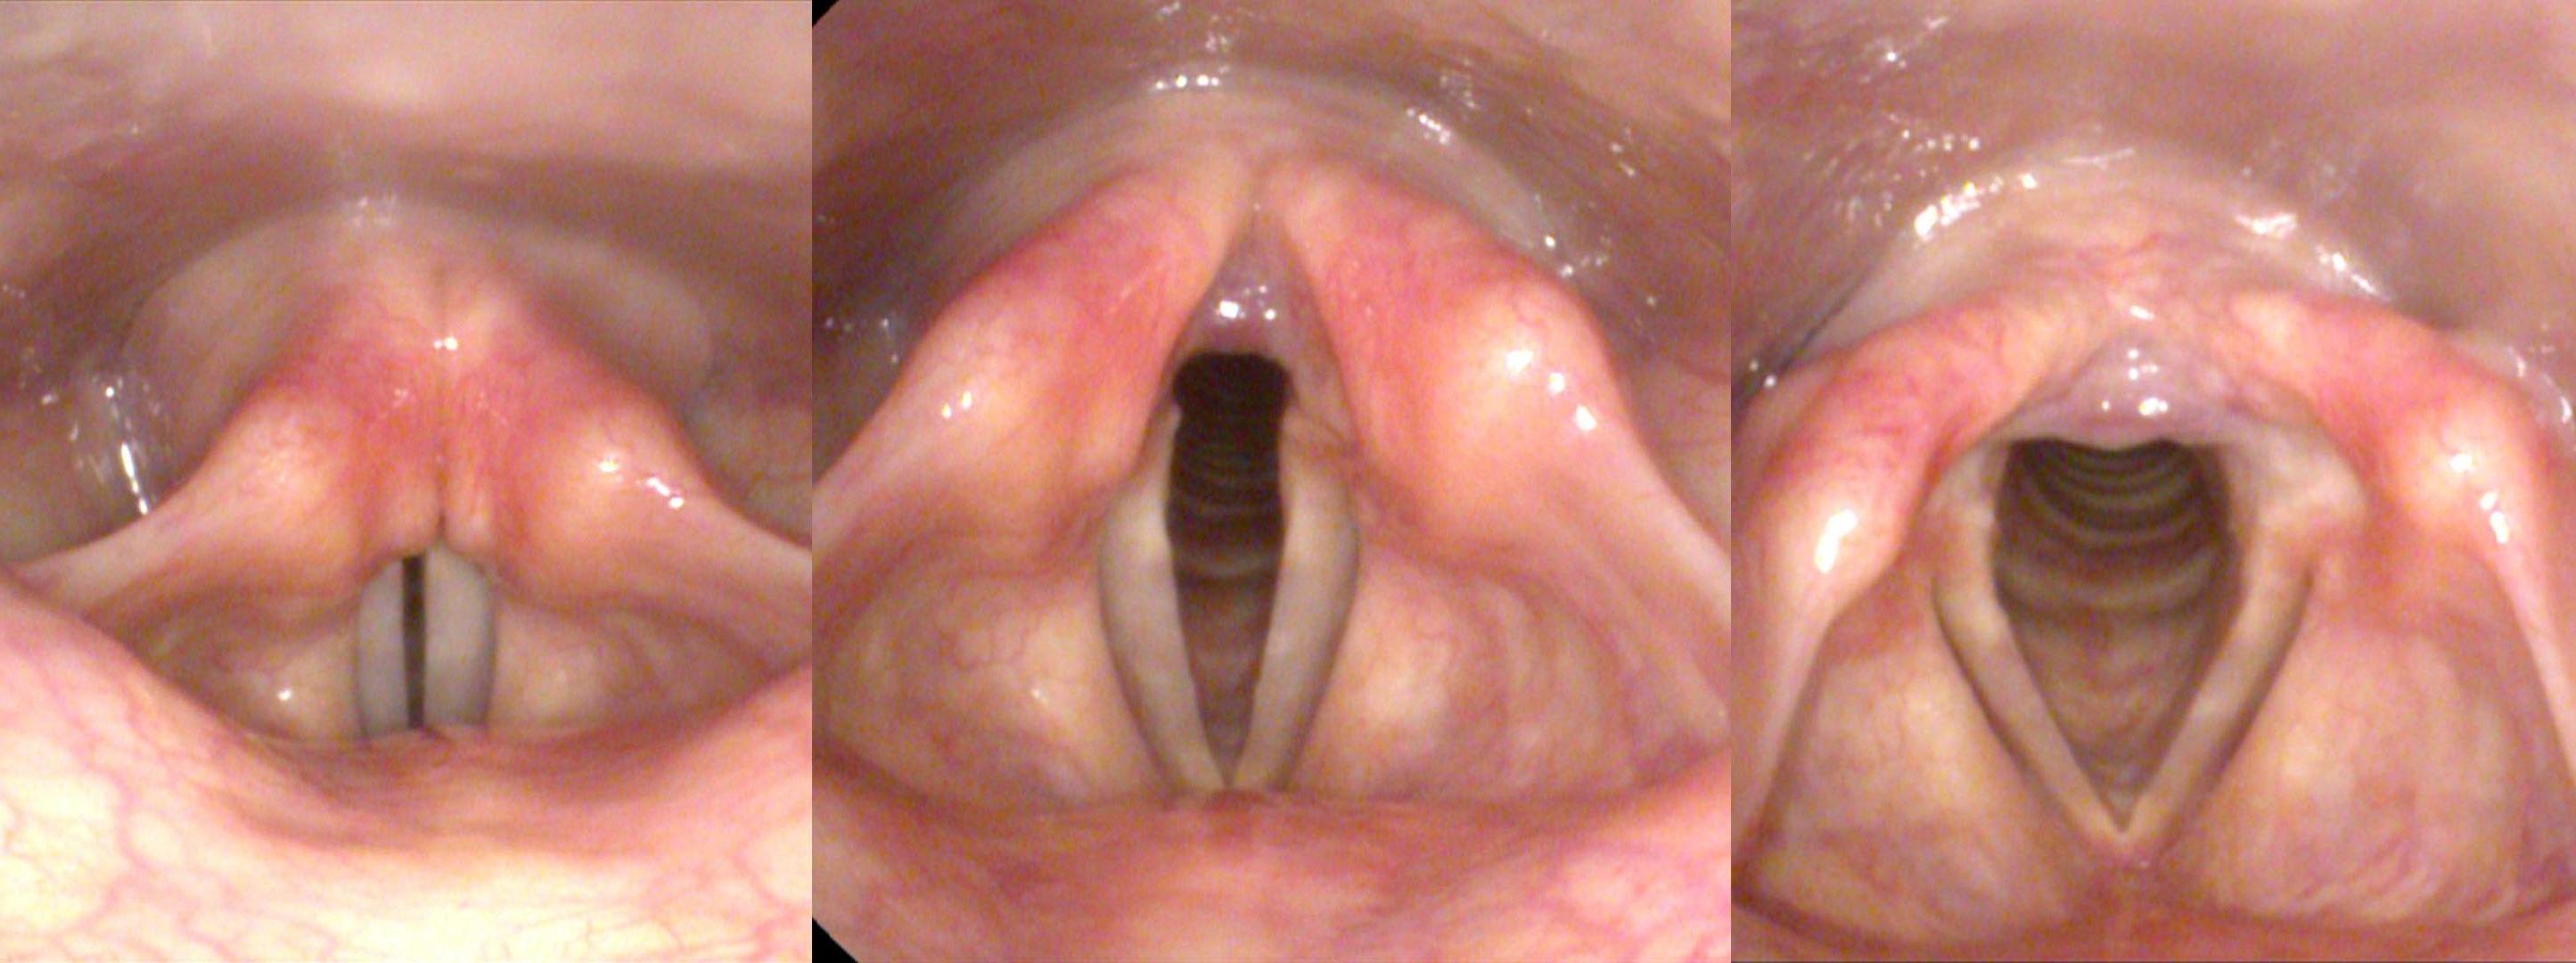

另外也可以從病人的其他個人史略知一二,例如: 最近有沒有接受過脖子方面的手術 (特別是甲狀腺)、最近有氣管內插管、脖子接受放射線照射、抽菸、停經、職業常常會使用到聲音等等,這些都可以幫助鑑別診斷,聲音沙啞不見得需要喉鏡檢查,但某些情況建議一定要做,例如: 血痰、呼吸窘迫、持續性吞嚥疼痛、有頸部腫塊、長期抽菸、神經學症狀、可能異物嗆入、術後持續沙啞、新生兒聲音沙啞、免疫不全、外傷後、體重減輕或聲音沙啞越來越嚴重等等,喉鏡可以幫助我們看到聲帶的振動、開合以及確認有無異物或是腫瘤,是非常準確的一項診斷工具,所以如果聲音沙啞一直沒好,請務必至耳鼻喉科門診接受檢查!!